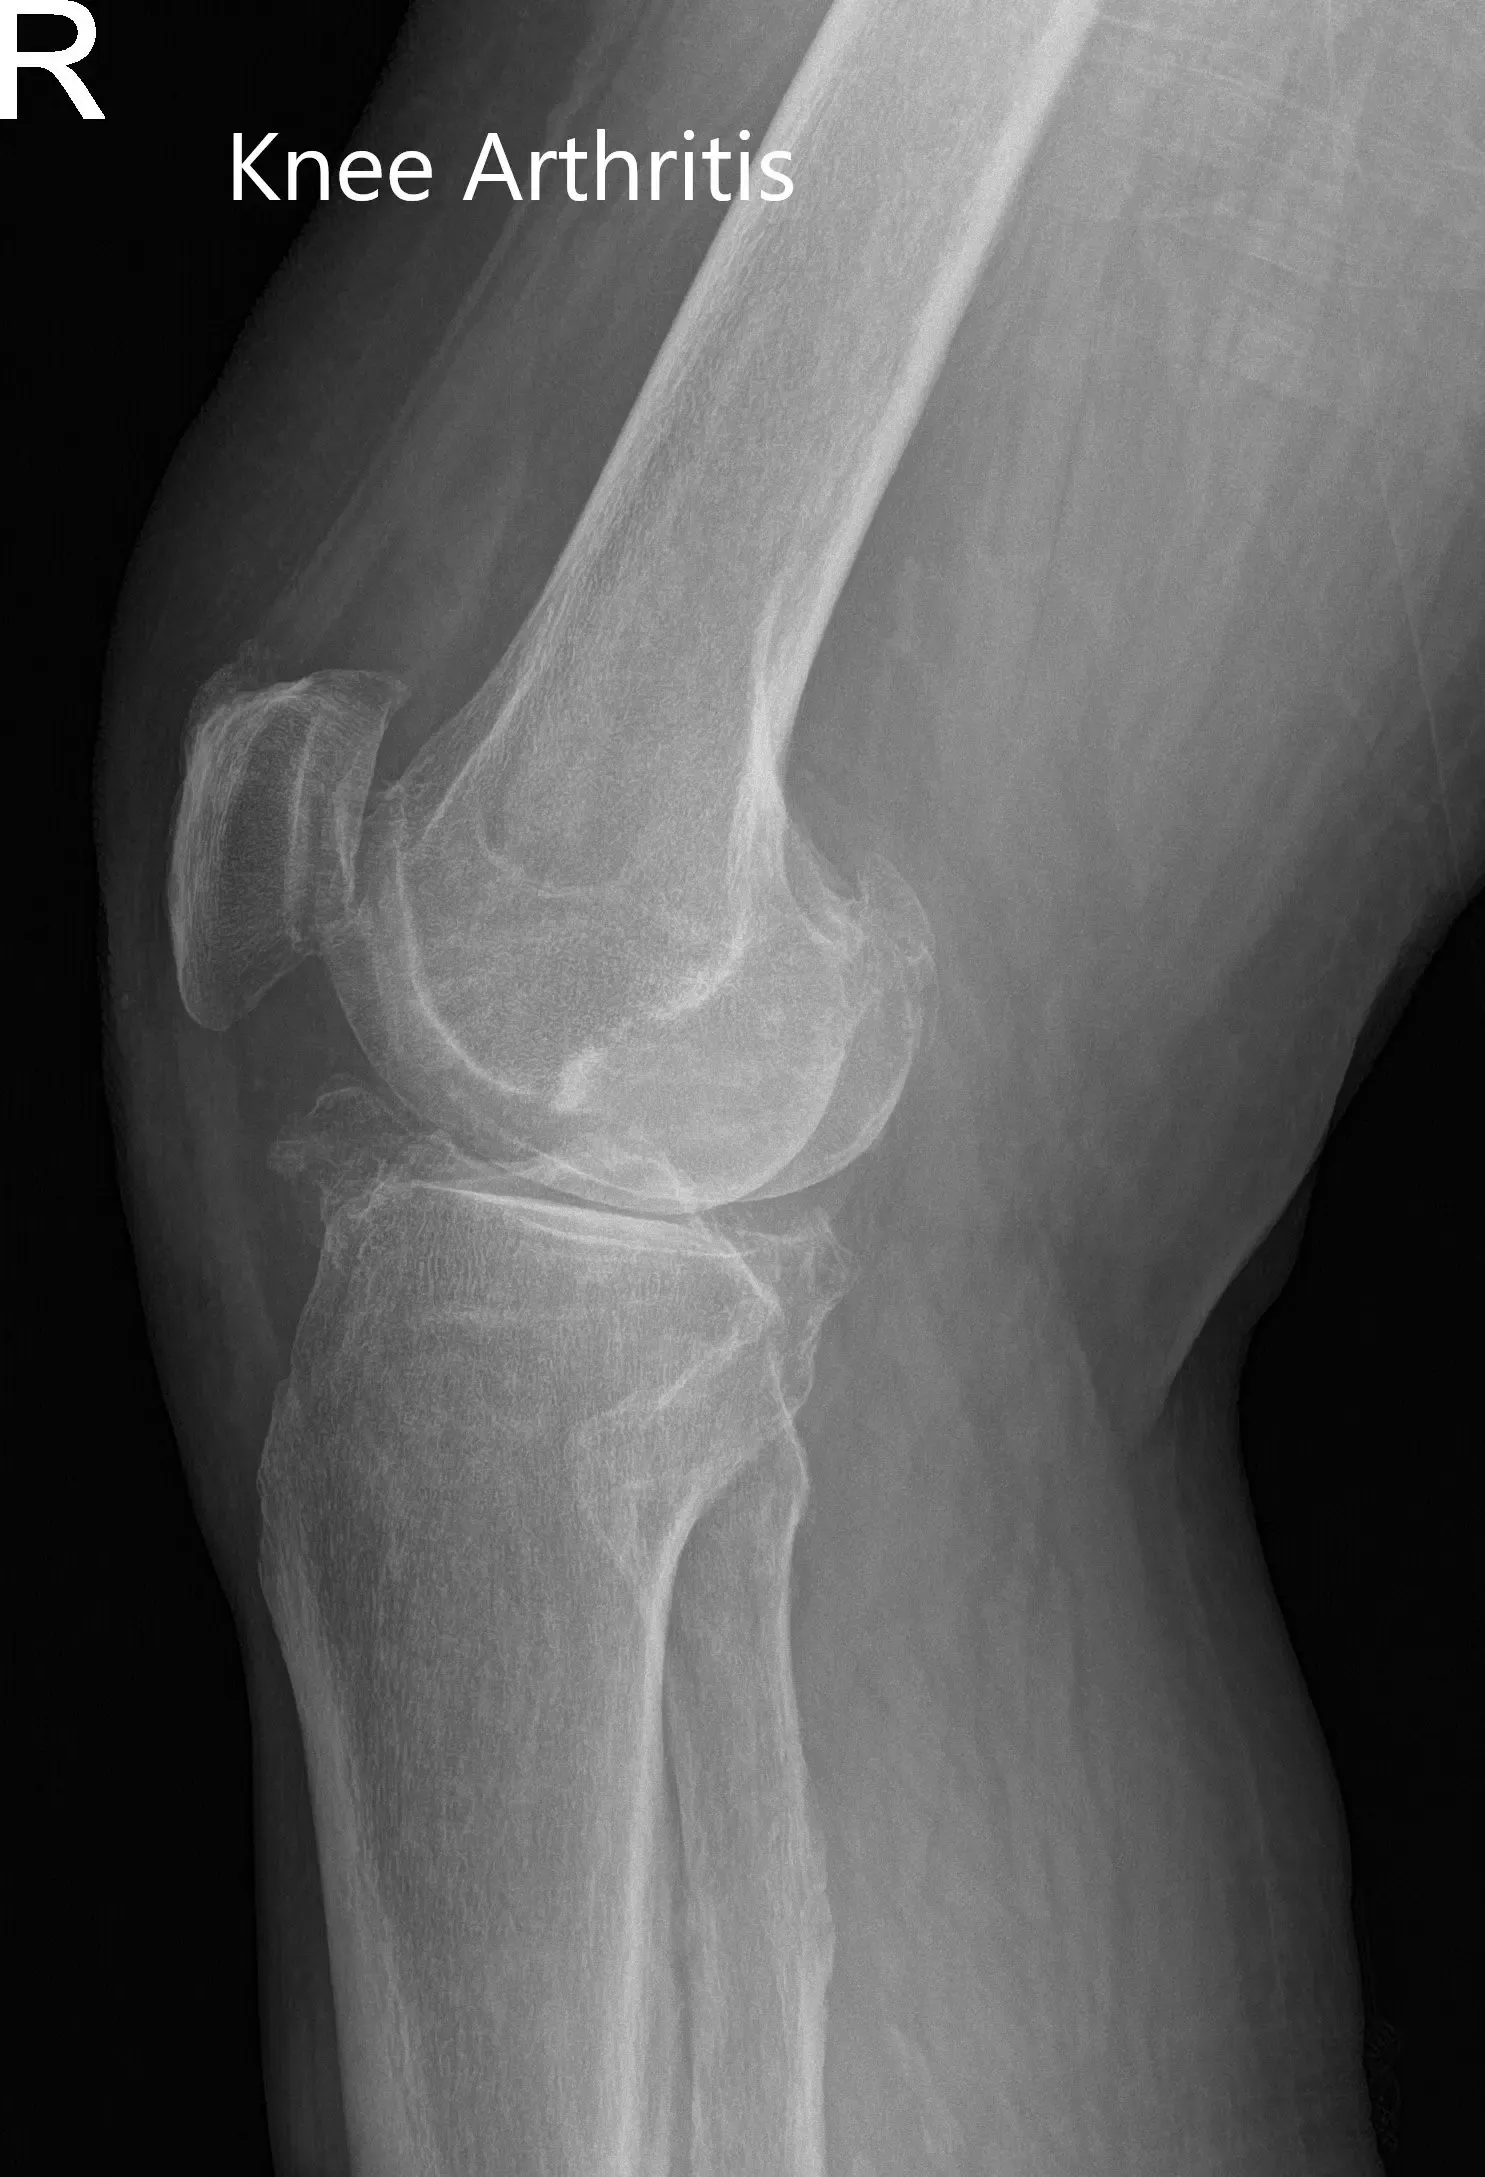

Los estudios de imagen revelaron una artritis bilateral severa de rodilla. La rodilla derecha estaba peor que la izquierda. Le recomendaron un reemplazo total de rodilla con instrumentos personalizados. Se discutieron extensamente con ella riesgos, beneficios y alternativas. Ella estuvo de acuerdo con el plan.

Radiografía de la rodilla derecha en vistas anteroposterior y lateral.